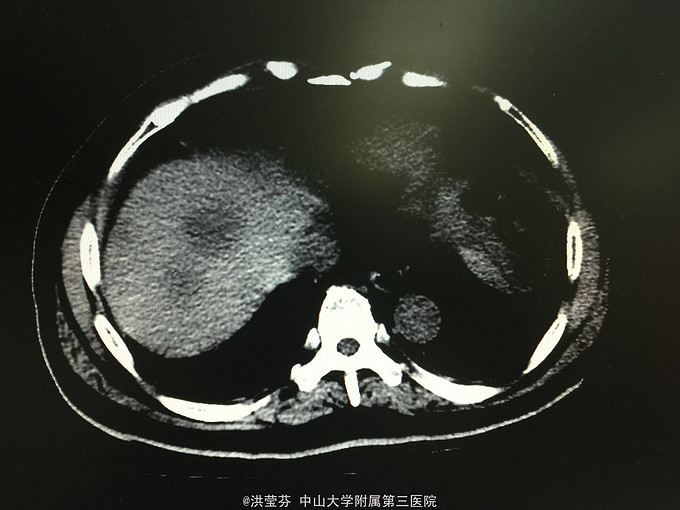

查体:上腹部轻压痛,无反跳痛。 辅助检查:上腹部CT增强提示:肝S2/3/4段恶性肿瘤,肝内多发子灶,肝左静脉及门静脉左、右支受侵;腹腔多发转移瘤;肝门部、腹膜后多发肿大淋巴结;门静脉海绵样变;少量腹水。胸部CT提示:1、双肺多发小结节,结合病史,考虑转移瘤;纵膈、双侧肺门多发肿大淋巴结。2.双肺炎症;左侧胸腔少量积液。CA125 555.1IU/nl,CA199 1093.5IU/nl。

诊断考虑胆管细胞癌可能性大,予完善肝穿刺,活检病理示:符合中分化腺癌,胆管细胞癌可能性大。免疫组化结果示:Hep(-),CK(+),CK19(+),CEA(-),CDX-2(-),DK20(-),Ki 67(约15%),TTF-1(-)。诊断明确肝内胆管细胞癌,IV期,无明显化疗禁忌,予GP方案化疗,辅以护胃、护肝、止吐等治疗。